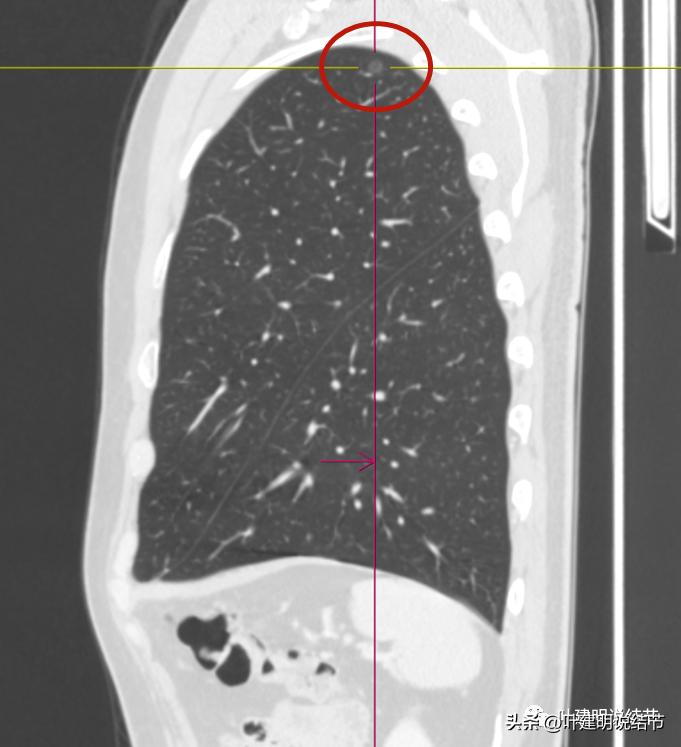

矢状位见病灶密度低,轮廓清,瘤肺边界清楚。

左侧磨玻璃结节红色圈起来的瘤肺边界清,有血管贴边,但整体密度低,没有实性成分,考虑仍是不典型增生或原位癌阶段,近期风险低,个人觉得最好先随访,因为可能很多年不变的,而且也可能再检出新的结节来。况且随访有进展再干预,效果也是一样的。右侧结节也是肿瘤范畴,但风险一样不高,建议同样半年到一年复查(其实1年也关系不大的)。意见供参考!